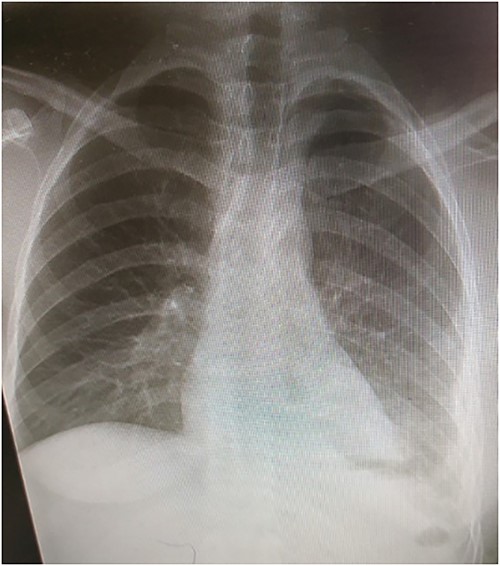

The patient was followed up with series of CXRs and patient is back to baseline (Fig. 5).